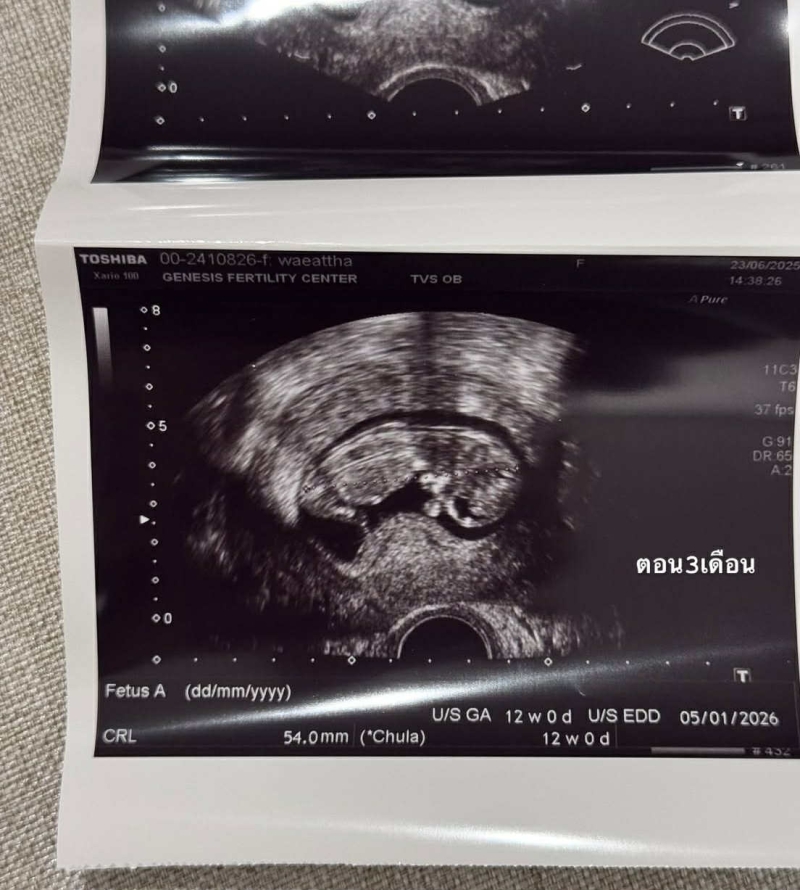

โดย เนย เผยว่า เธอ หายไปจากโซเชียลช่วงหนึ่งเพราะว่า ตอนนี้ ท้องเกือบ 4 เดือนแล้ว ก่อนหน้านี้ เธอ มีการเตรียมตัวอย่างดี ทั้งการดูแลสุขภาพ การกินอาหารคลีน ออกกำลังกายสม่ำเสมอ และนอนเร็ว แต่ยังประสบปัญหา บ้ายบายน้อง ไปถึงสองครั้ง ทำให้ เธอ ตัดสินใจไปหา คุณหมอมิงค์ ที่คลินิก GFC ผลการตรวจออกมาพบว่า เธอ และ สามี มีโรคทางพันธุกรรมแฝง

หลังจากการตรวจพบปัญหา เนย จึงตัดสินใจทำการรักษาด้วย ICIS ที่รวมถึงการคัดโครโมโซม และตรวจคัดโรค เธอ ได้รับการดูแลอย่างดีจาก คุณหมอมิงค์ และ ทีมงาน จนกระทั่งในที่สุดกระบวนการประสบความสำเร็จ และ ตอนนี้ ท้อง 4 เดือนแล้ว เบบี๋ ของ เธอ แข็งแรง และดิ้นเก่ง